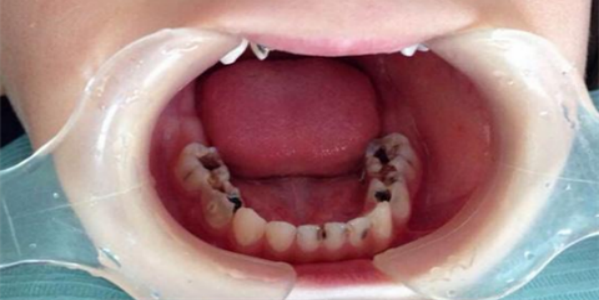

治疗龋齿有什么重要性 龋齿在世界上是常见病、多发病,并且可以诱发出多种慢性疾患。乳牙可以患龋齿,恒牙也可以患龋齿。龋齿是细菌从牙齿感染进入人体内的一个开端。极高的翻齿发病率,使许多牙... 牙齿治疗 仙千风 748 2023-12-19

龋齿有什么危害 龋齿是威胁人类身体健康的一种常见病、多发病。根据我国的大量调查发现,我国人民患龋率为37.3%,患龋者平均每人有龋齿2.47颗。由此推算,我国有龋病患者约... 牙齿治疗 鄂昊英 643 2023-11-28